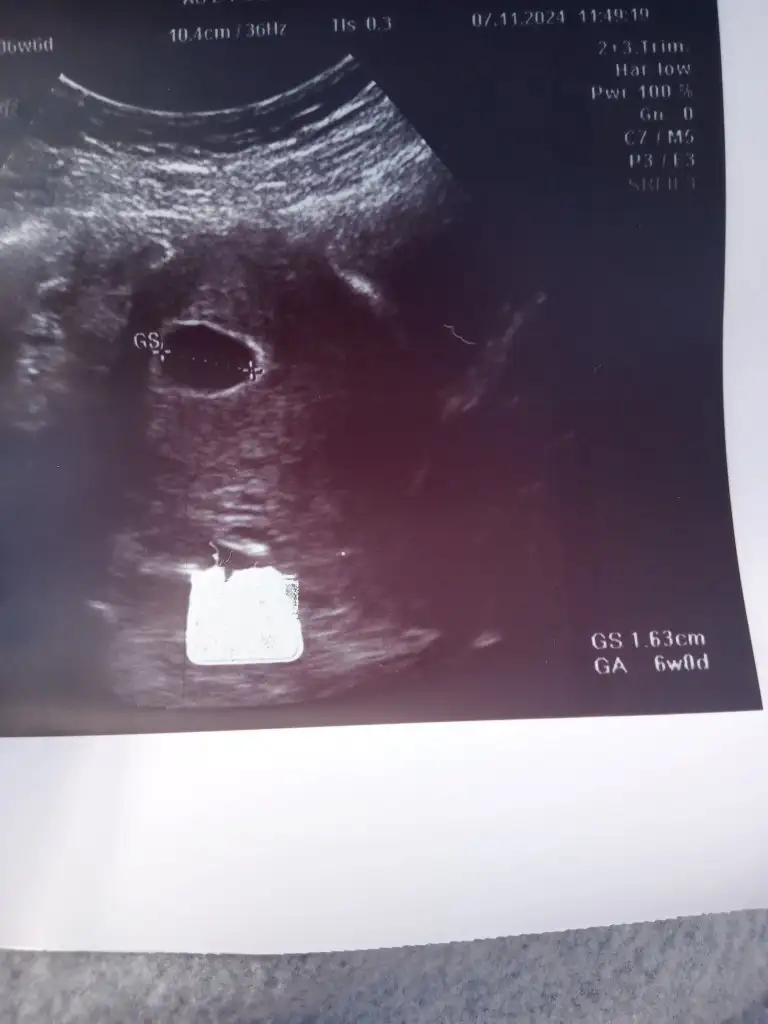

Ultrasonu da asistanı (karından) yaptı. Kendi de takip edip yönlendirdi. Haftasıyla uyumlu rahim içine konuşlanmış keseyi görebiliyoruz dedi. On gün sonra bebek ve kalp atışı için çağırdı. Rutin tahliller için 3 tüp kan, idrar tahlil ve kültürü için numune verdim. Sonuçlar çıkınca da gel bakalım dedi.

Evet şimdi çıktım daha önceki yaptığımız kan testine göre 4 haftalık sat a göre 6 haftalık dedi karından baktı kese var ama bebek yok geç döllenme nedeniyle goremeyebiliriz dedi haftaya gel yada boş gebelik dedi haftaya belli olur dedi kese sağlıklı ve 6 haftalık gözüküyor dedi yine cevapsız kaldım daha fazla soruyla bakalim

kese 5-6. Haftalar

bebek kalp atışı 7-8. Haftalarda.

Bu şekilde şu an kızlar bakalım haftaya netleşir sanırım bu sefer sancılı geçiyor süreç her anlamda hayırlısı